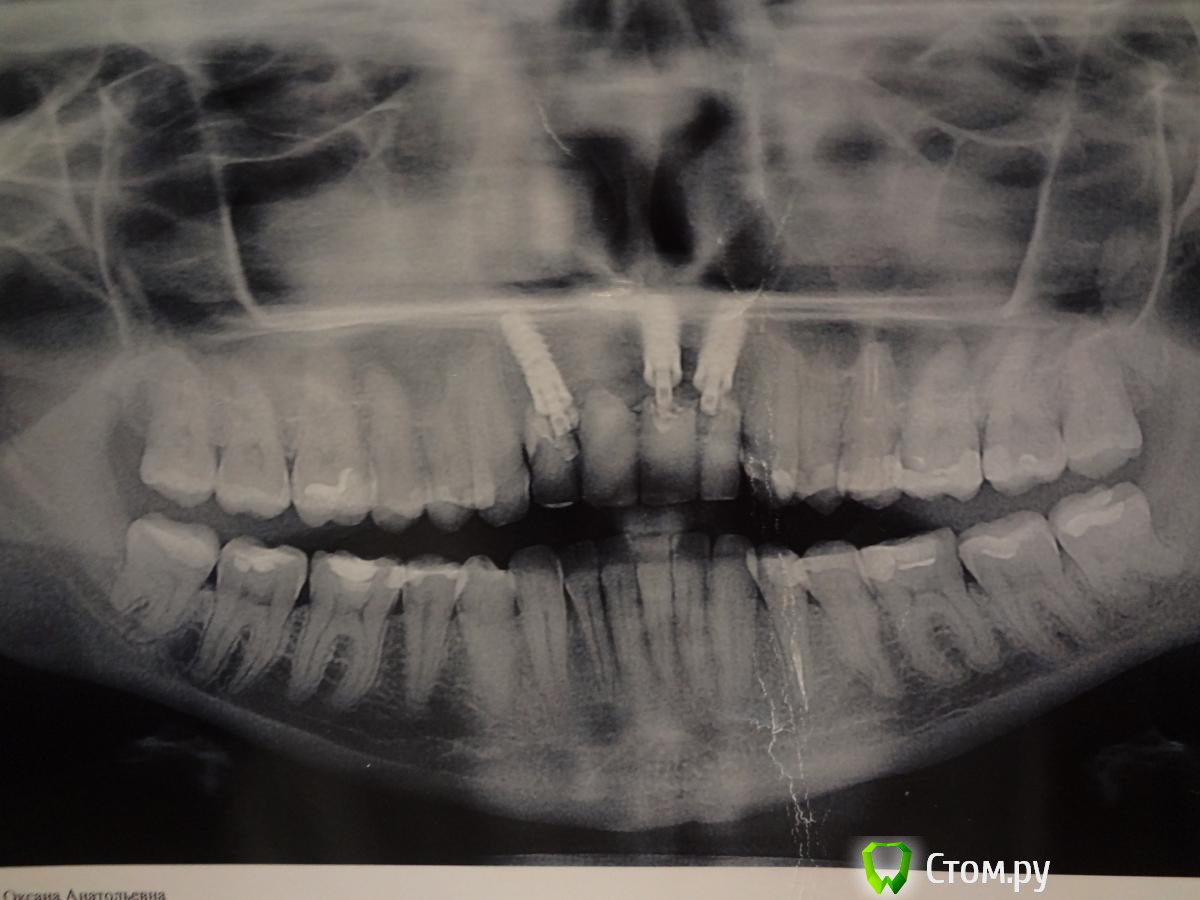

Яркая брюнетка Опубликовано 6 декабря, 2013 Поделиться Опубликовано 6 декабря, 2013 (изменено) Здравствуйте.У меня отсутствуют 4 верхних передних зуба. Поставили на их место 3 импланта Impla.Случай у меня довольно не простой, так как это уже 3 моя имплантация , которая наконец то оказалась удачной. До этого костная ткань была разрушена кистами на корнях зубов , были свищи, неоднократные чистки и в итоге только третья имплантация после подсадки костной ткани оказалась удачной.Сейчас у меня стоит мост из 4-х зубов на 3-х имплантах. Но это довольно не прочная конструкция. Пластмассовые зубы и пластмассовые абатменты. Ими я кусаю только мягкие продукты, а то не выдержат.К сожалению, сейчас по финансовым соображениям не могу поставить постоянную конструкцию (хочу из диоксида циркония). Но переживаю,что из за недостаточной нагрузки на зубы и импланты кость вокруг имплантов начнет убывать С временной конструкцией хожу уже 9 месяцев.Скажите ,пожайлуста, правда ли при недостаточной нагрузке кость вокруг импланта разрушается? И как быстро это происходит? Ведет ли это к потере имплантов? Изменено 6 декабря, 2013 пользователем Яркая брюнетка Ссылка на комментарий

Яркая брюнетка Опубликовано 7 декабря, 2013 Автор Поделиться Опубликовано 7 декабря, 2013 (изменено) В электронном виде не было, поэтому сфотографировала распечатанный электронный вариант. Изменено 7 декабря, 2013 пользователем Яркая брюнетка Ссылка на комментарий